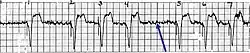

Exemplo de ECG do dispositivo a) flutuando livremente no VD b) em contato com a parede do VD

Exemplo de ECG do dispositivo a) flutuando livremente no VD b) em contato com a parede do VD -